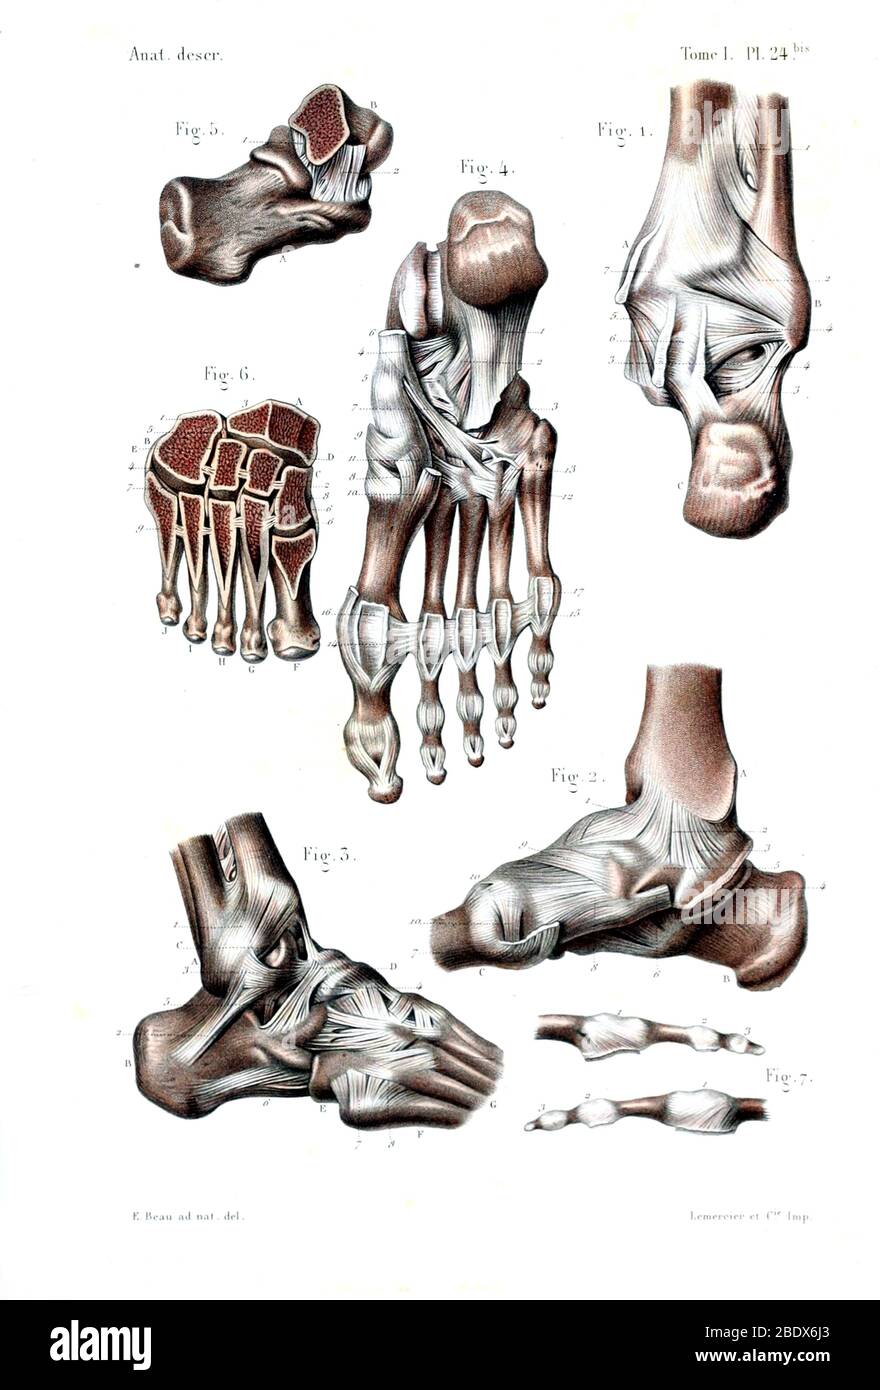

RF2ABM669–La médecine et les soins de l'illustre le tableau, les droits de l'anatomie du pied : Peau et tissus ectodermaux, os, muscles nerfs, vaisseaux sanguins